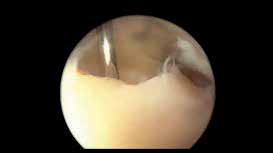

Arthroskopie und Gelenkdebridement

Das Sprunggelenk ist mittels Arthroskopie gut zu erreichen. Durch die oft posttraumatisch bedingten lokalen Knorpelschäden oder Osteonekrosen kann primär eine alleinige arthroskopische Therapie erfolgreich sein. Das reine Gelenkdebridement wird jedoch kontrovers diskutiert und zeigt analog zu den wissenschaftlichen Untersuchungen am Kniegelenk zur Gelenklavage bei Gonarthrose keine langfristige Schmerzlinderung 34. Dagegen kann beim Vorliegen ätiologisch bedingter degenerativer Gelenkveränderungen wie osteophytären Anbauten, freien Gelenkkörpern, vernarbter und hypertroph-entzündlicher Synovia oder fokalen osteochondralen Defekten (Abb. 5) durch das gezielte operative Gelenkdebridement eine signifikante und langfristige Schmerzreduktion erreicht werden 35.

Auch bei Osteophyten an der vorderen Tibiakante ist die arthroskopische Abtragung die Methode der Wahl. Bei dieser Form des Impingements werden neben dem Zelldetritus störende mechanische Knochenanbauten oder Weichgewebe wie eine traumatische mediale Plica entfernt und weisen postoperativ signifikant verbesserte Ergebnisse bzgl. Schmerzreduktion und Funktion auf 36. Beim Abtragen von vorderen Tibiakantenosteophyten darf nur so viel abgetragen werden, dass daraus keine Instabilität des Sprunggelenks resultiert.